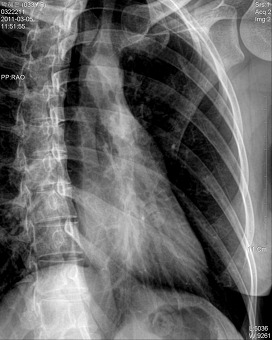

*흉부 측방향 촬영법(Chest lateral )

검사목적

Left Lateral에서는 좌측 심장과 폐의 병소를, Rignt Lateral에서는 우측 심장과 폐의 병소를 진단하기 위해 사용

Central Ray

T-6 높이의 정중면에 수직으로 입사

Film Size

14 " X 14 ", 14 " X 17 "

Position

환자는 가능한 Erect Position을 취한다.

환자는 Lateral Position을 취하고 인접한 견부를 격자에 밀착 한다

Film의 상연이 양측 견부의 위 4cm 정도에 놓이도록 Detector의 높이를 조절한다

액와중앙선은 격자 중앙선 뒤  5cm 정도에 놓이게 조정한다.

Check Point

척주뒤의 Rib이 겹쳐서 보여야 한다

흉골이 회전되지 않아야 한다

Apex, CP angle은 포함되어야 한다

심장과 diaphragm의 윤곽은 선명하게 나타나야 한다

Hilum이 영상의 중앙에 나타나야 한다